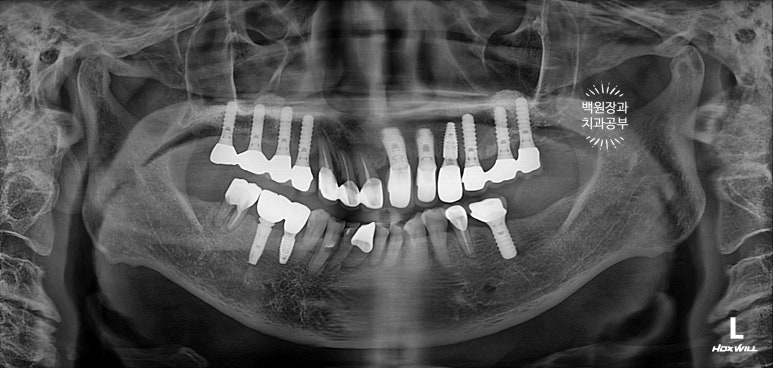

잘 보시면, 임플란트가 총 위턱에 9개, 아래턱에 2개 되어있는데 대부분이 아주 유명한 외국 임플란트 제품들입니다. 특히나 위턱 어금니는 스트라우만 standard 제품으로, 제가 가장 신뢰하는 제품 중 하나입니다.

무려 20년이 넘으셨다고 했는데... 임플란트 주위염 하나 없이 너무너무 잘 사용하고 계시더라구요.

처음 오셨을 때, 치과용 파노라마 사진에서 파란색 화살표로 표시해둔 두 치아 - 왼쪽 위 송곳니와 오른쪽 아래 작은어금니가 뿌리만 남아있는 상태로 내원하셨어요.

특이할만한 점이, 두 치아 모두 신경치료와 크라운 치료를 받았던 치아였다는 것... 역시나 신경치료는 치아 건강에 그리 좋지 않음을 알 수 있습니다..

화살표로 표시해놓은 것들이 이번에 새로 임플란트로 채워넣어진 자리입니다!

위턱의 씹는면을 보시면, 스트라우만 임플란트로 아주 깔끔히 치료된 것을 보실 수 있습니다.

옛날에 치료받았던 스트라우만 임플란트는 이제 오래되어... 조금 깨지도 닳은 것은 보이나, 사실 기능하는데는 문제가 없었어요. 20년이 넘었음에도 이렇게 훌륭한 임상결과를 보이는 스트라우만 임플란트. 정말 최고임을 직접 보여주고 있었습니다. 진짜 올타임 넘버원 임플란트입니다.

아래 또한 깔끔하고 예쁘게 임플란트 크라운이 제작되었어요. 특징이라면 기존의 임플란트와 보철물을 묶어서 제작해드림으로써 음식이 끼는 것을 확실히 막아드렸다는 것입니다!